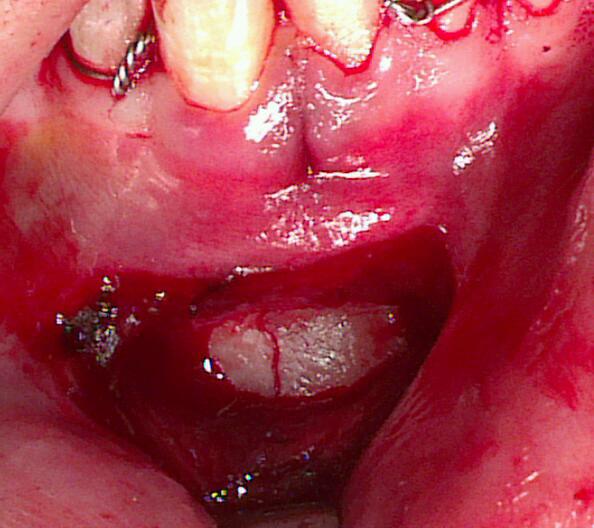

Results: The most frequent bone fractured was the mandible, which accounted for 106 cases 49.5%, followed by 15.4% of pan facial (full house) fractures and 15.4% of Zygomatic complex fracture. The associated mid face fractures were found in 12.6 % and isolated nasal bone fractures were found in 1.5% cases. The most common cause of injury was RTAs 58.4%, followed by accidental falls 24%, FAIs 6.1%, interpersonal violences 2.8% and sports and other injuries were 8.4% cases. Employees 49.5% and students 31.3% in age groups 20-40 years are mostly affected by RTA, while falls 14.4% are more common in age group less than 20 years. ORIF alone 43.9%, MMF±suspension 38.8% and ORIF with MMF 14.5% cases were the main mode of treatment in our centre.

Conclusions: In this case series, mandible was the most commonly fractured facial bone; RTAs especially by motorbike and chigchi rikshaw were the most common etiological factors. Results could be influenced by the personal and working environment.

IMAGES